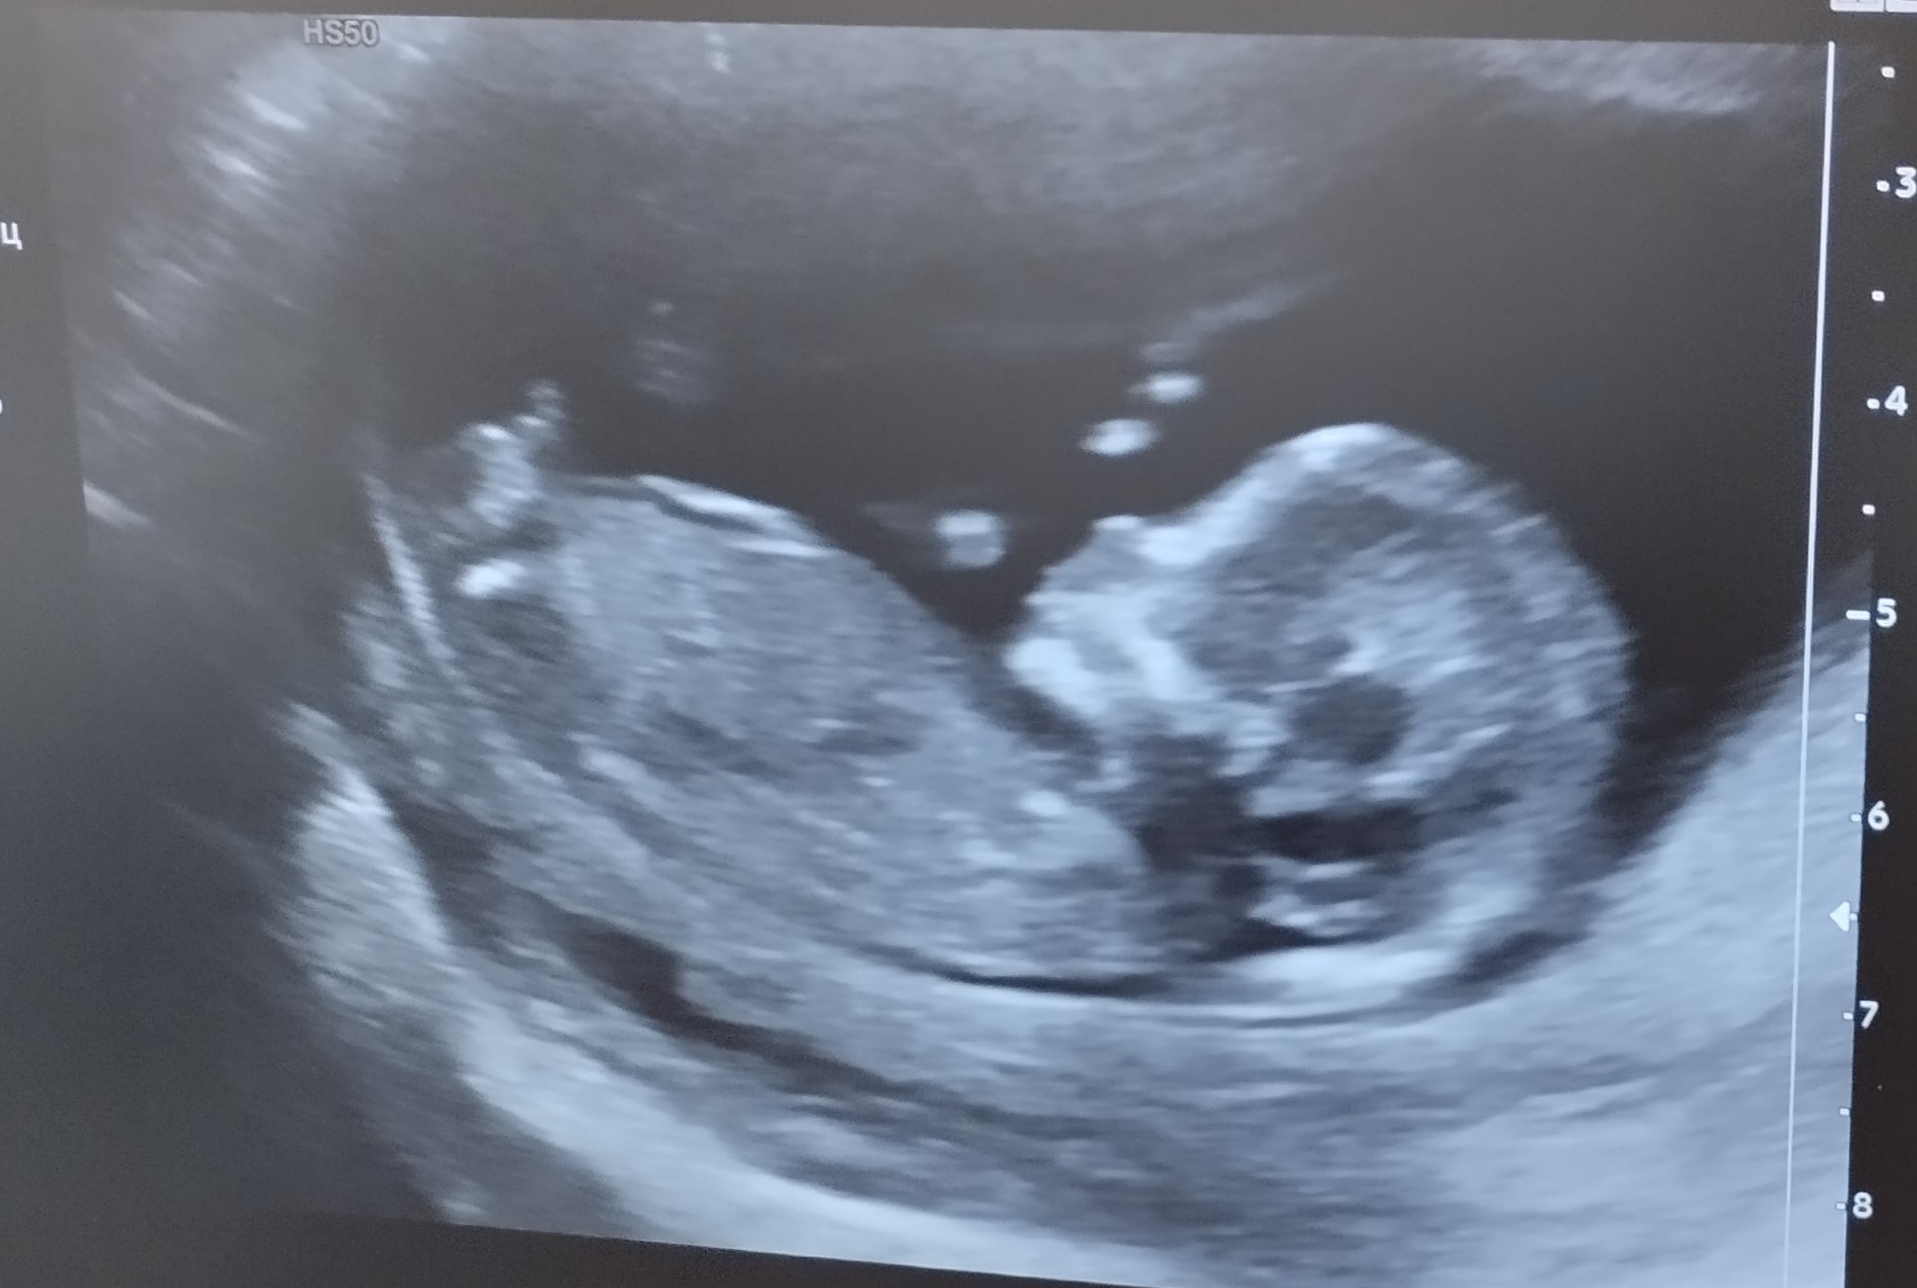

Первый скрининг позади!

Прям мальчик.. даже лицо мальчика 😅

Nina Yurievna, только не говорите, что вы по фотке поняли 😂 я даже ноги-руки не вижу

Моня, нееет, по вашему голубому кружочку🥰